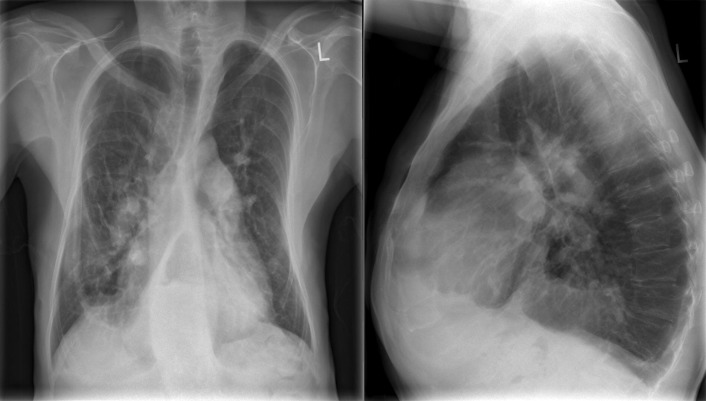

A patent foramen ovale is present in 25% to 30% of the adult population ( Figs. 18-1 to 18-4 ). Any magnitude of shunting across it in normal circumstances is undetectable radiographically. Percutaneous patent foramen ovale closure devices are fairly commonly inserted and are radiographically evident.